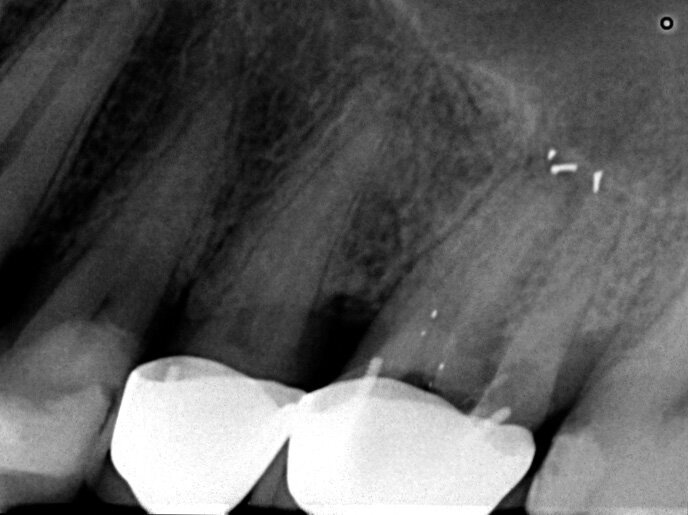

Un patient avait été adressé au cabinet en raison de problèmes associés à la fracture d’une lime. Il était pilote de ligne et se plaignait d’écoulements nasaux purulents lorsqu’il était en vol. La radiographie pré-opératoire (Fig. 1) a distinctement montré la présence de deux fragments d’une lime fracturée dans les canaux mésiaux et d’un cône traversant l’apex de la racine palatine. Après l’imagerie CBCT avec iCAT, il est apparu clairement que le sinus gauche était presque totalement rempli de liquide inflammatoire (Fig. 2) et que le cône présent dans le canal palatin pénétrait dans le sinus. Sur l’image de reconstruction multi planaire (MPR), nous pouvions également distinguer les deux fragments de lime fracturée dans les deux canaux mésiaux (Figs. 3 et 4) et aussi un autre fragment dans le sinus sans aucun contact avec le canal (Fig. 5). L’utilisation de différents filtres nous a permis de visualiser les fragments de lime (Figs. 6–9), ainsi que l’inflammation et le fragment de lime fracturée à l’intérieur du sinus. Nous avons également mieux perçu la position du cône qui émergeait du canal palatin et pénétrait dans le sinus.